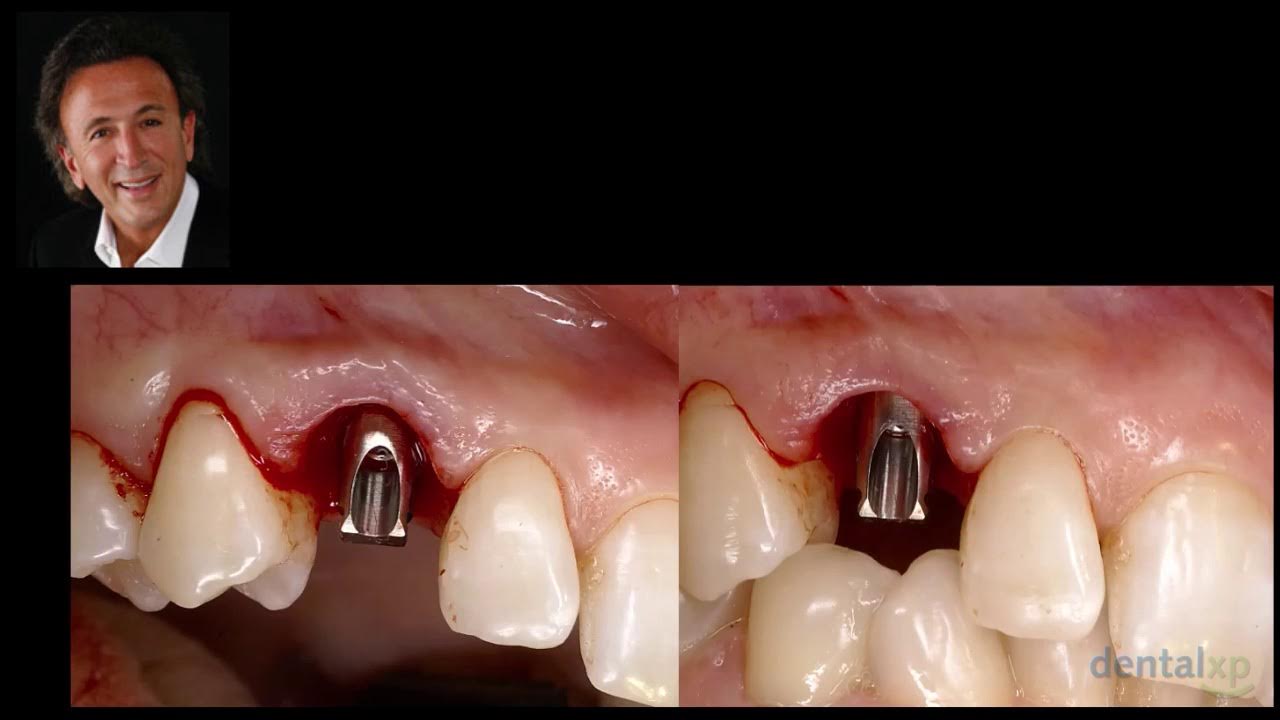

SOCKET SHIELD DOUBLE GUIDE technique CONNECT ABUTMENT YouTube Implant Socket Shield Technique the aim of this review is to present the currently available studies on the treatment outcome of socket shield technique (sst). the socket shield procedure is a new technique of partial extraction therapy for immediate implant placement. the primary objective of this systematic review was to answer two fundamental questions: the socket shield technique can be. Implant Socket Shield Technique.